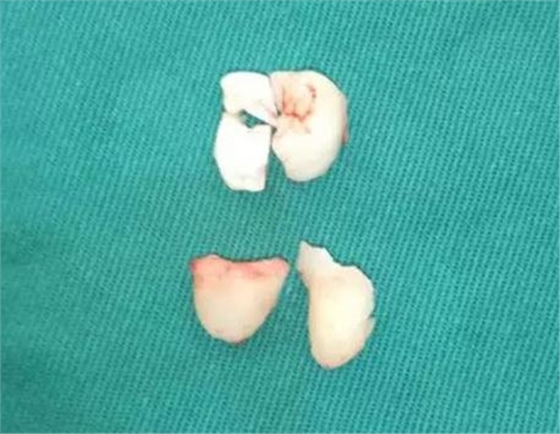

使用普通手機(jī)加裂鉆沿遠(yuǎn)中冠中間磨除大部分冠組織,取出。

使用彎?rùn)C(jī)開始分殘冠,使牙根近遠(yuǎn)中向的分開,使用牙挺挺松后,取出遠(yuǎn)中根。

去冠近中的骨壁,挺出之前分離出的殘冠,分次取出近中牙根,取刮匙刮牙槽窩。探查是否有剩余牙體組織。